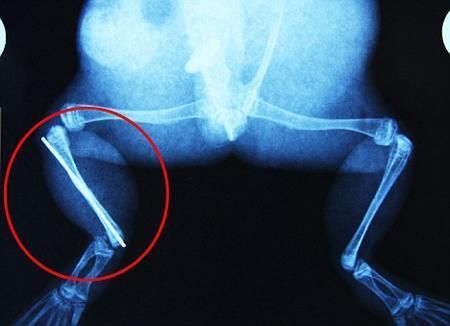

環(huán)球網(wǎng)4月2日報(bào)道 據(jù)《每日郵報(bào)》報(bào)道,上個月,南非大牛蛙布魯萊的右小腿被鄰居家的一只狗咬到,導(dǎo)致粉碎性骨折,現(xiàn)在經(jīng)過2個小時的手術(shù),它的斷腿已經(jīng)被接上,它也因此成為有史以來第一只通過外科手術(shù)用鋼針接上斷腿的青蛙。

野生生物專家安妮經(jīng)常為學(xué)校寫教材,她認(rèn)為這是人類第一次通過手術(shù)給一只青蛙接斷腿。在手術(shù)開始階段,獸醫(yī)把少量給狗用的麻醉藥注入到這只青蛙體內(nèi),讓它失去知覺。然后他在布魯萊的斷腿上切開一個小口,把一根小鋼針植入腿里。最后獸醫(yī)給它縫了9針,把切口縫合在一起。僅僅幾周后,布魯萊就能在安妮家附近活動了。這只青蛙大約已有25歲,主要以嚙齒動物、蛇和其他青蛙為食。布魯萊所屬的牛蛙種群正在不斷減小,目前只能在非洲南部的濕地里才能看到這種青蛙。

安妮有2個孩子,她已經(jīng)從事20多年兩棲動物保護(hù)工作。她認(rèn)為鄰居家的狗狗在把布魯萊從地下刨出來的時候,它正在地下冬眠、她說:“世界上只有這個地區(qū)能看到這種牛蛙,這種青蛙現(xiàn)在變得越來越稀少。因?yàn)槲覐氖乱吧锉Wo(hù)工作,因此認(rèn)識很多兩棲動物專家,但是以前他們誰也沒見過這種事情。看到布魯萊越來越健康我非常開心,F(xiàn)在還需要一段時間,它的金屬腿和它的骨骼才能融為一體,那時布魯萊會跟以前一樣健康。我們認(rèn)為這個過程需要幾周時間,但是一旦它完全康復(fù),我希望把它放歸大自然,讓它重新回到它最鐘愛的濕地里。”